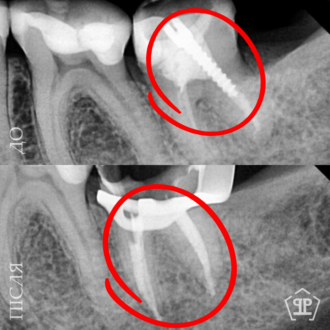

Пациент нуждался в повторном лечении корневых каналов из-за осложнений предварительного лечения. Выполнено извлечение анкерного штифта, перелечивание корневых каналов, очищение и пломбирование с учетом анатомических особенностей зуба.

Во время диагностики обнаружен отлом фрагмента инструмента в корневом канале. Выполнено его безопасное извлечение, повторное перелечивание каналов, очистку и герметичное пломбирование.

Перелечивание с удалением двух переломанных инструментов. Пациент обратился с осложнением предварительного эндодонтического лечения. В каналах были обнаружены два переломанных инструмента. Выполнены их удаление и пломбирование каналов с соблюдением современных эндодонтических протоколов.